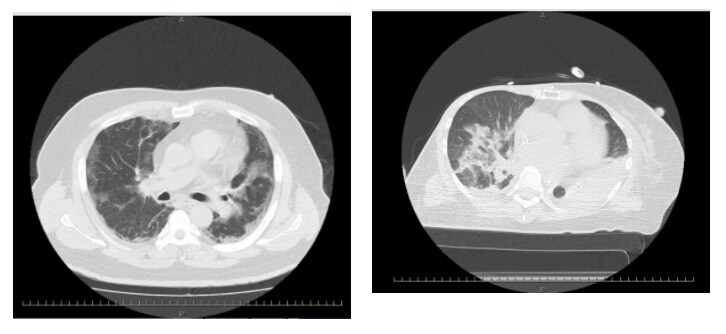

実は死亡者の多いオミクロン株、軽症・弱毒は大うそ